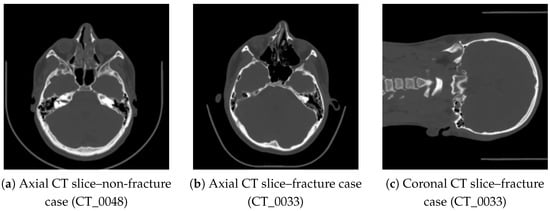

To illustrate the visual variability in the dataset, three representative CT slices are presented in Figure 1. Basic intensity-based features computed for these slices are summarized in Table 1.

Figure 1. Representative CT slices included in the dataset: (a) healthy case, (b,c) fracture case showing disruptions of the orbital rim and anterior maxillary wall.

Table 1. Example intensity-based features calculated for the representative CT slices shown in Figure 1.

ImageMean HUStd HUP10P90Entropy

CT_0048 (axial, no fracture)145.238.792.1201.54.83

CT_0033 (axial, fracture)158.452.978.4225.65.27

CT_0033 (coronal, fracture)162.155.380.3229.45.34